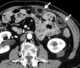

Calcified omental fat

Epiploic appendagitis (EA) is an uncommon, benign, self-limiting inflammatory process of the epiploic appendices. Other, older terms for the process include appendicitis epiploica and appendagitis, but these terms are used less now in order to avoid confusion with acute appendicitis. [Source: Wikipedia ]